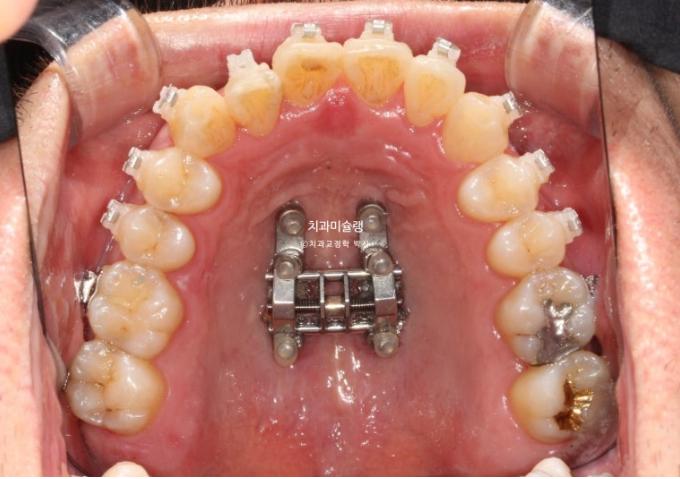

이 경우 악궁확장 장치를 써서 덧니를 비발치로 배열하기도 합니다.

오늘 포스팅은 30대 후반의 성인에서 악궁확장장치를 사용하여 발치없이 심한 덧니를 해결한 증례를 보여드리겠습니다.

아울러 MSE 악궁확장장치로 입천장 뼈가 벌어졌을 때 일어나는 변화들에 대해서도 소개드릴게요.

따라서 상악 악궁확장장치를 통해 덧니를 해결하기로 합니다.

30대 후반이라는 나이와 성별을 고려하면 악궁확장 실패 가능성이 커서 악궁확장장치 심는 날 봉합부를 따라 뼈를 느슨하게 만드는 corticopuncture도 함께 시행해야 합니다.

24년 10월 악궁확장이 성공하여 앞니 사이가 벌어졌습니다.

24.10

이렇게 앞니가 벌어지면 잘된 일입니다.

악궁확장 장치는 약 6개월간 유지하여 벌어진 봉합부에 다시 단단한 뼈가 차오르도록 도모합니다.